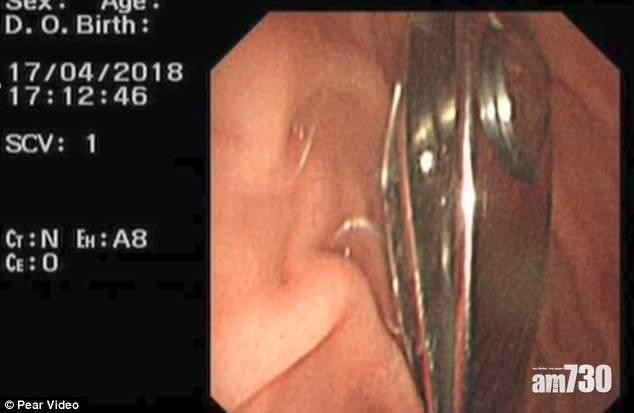

【好危險啊!】16個月大男嬰誤吞2.4吋長指甲鉗

中國長春市一名16個月大男嬰,誤吞2.4吋長指甲鉗,入院以內窺鏡從胃部取出指甲鉗,男嬰無大礙。

男嬰母親表示,當時剛幫兒子修理完指甲,剛要清理,兒子突然從她身上取了指甲鉗玩,想要取回時,兒子竟跟她追逐起來,其後更將指甲鉗放到口中吞掉。母親立即帶男嬰到醫院,X光片清晰可見男嬰胃部有一把指甲鉗,醫生立即為他進行手術,以內窺鏡取出指甲鉗。